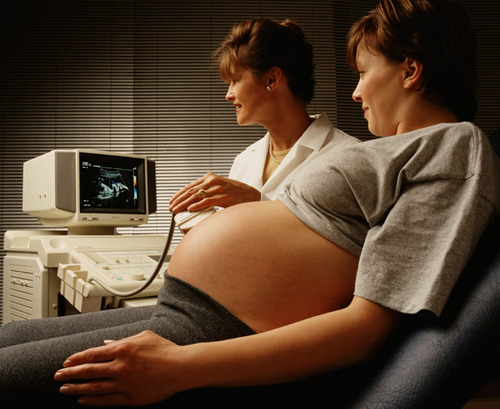

X光、CT、B超、核磁共振……这些都是医疗中常用的影像学检查法,但是它们有什么区别,看什么病应该照什么影像呢?